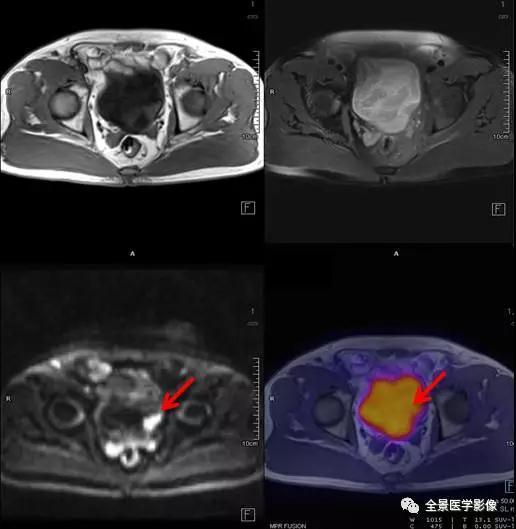

膀胱癌

◆ 案例:老年男性,排尿中断半年余,无血尿。膀胱左后壁局限性增厚,病灶以宽基底与膀胱壁相连,长径约 1.8 cm。膀胱镜证实为膀胱癌。

点评:

膀胱癌是泌尿系统最常见的恶性肿瘤,较为明确的两大致病危险因素是吸烟和职业接触芳香胺类物质。绝大多数的膀胱癌患者最初的临床表现是血尿。本例患者无血尿症状,经 PET/MR 检查偶然发现了膀胱内占位病变。